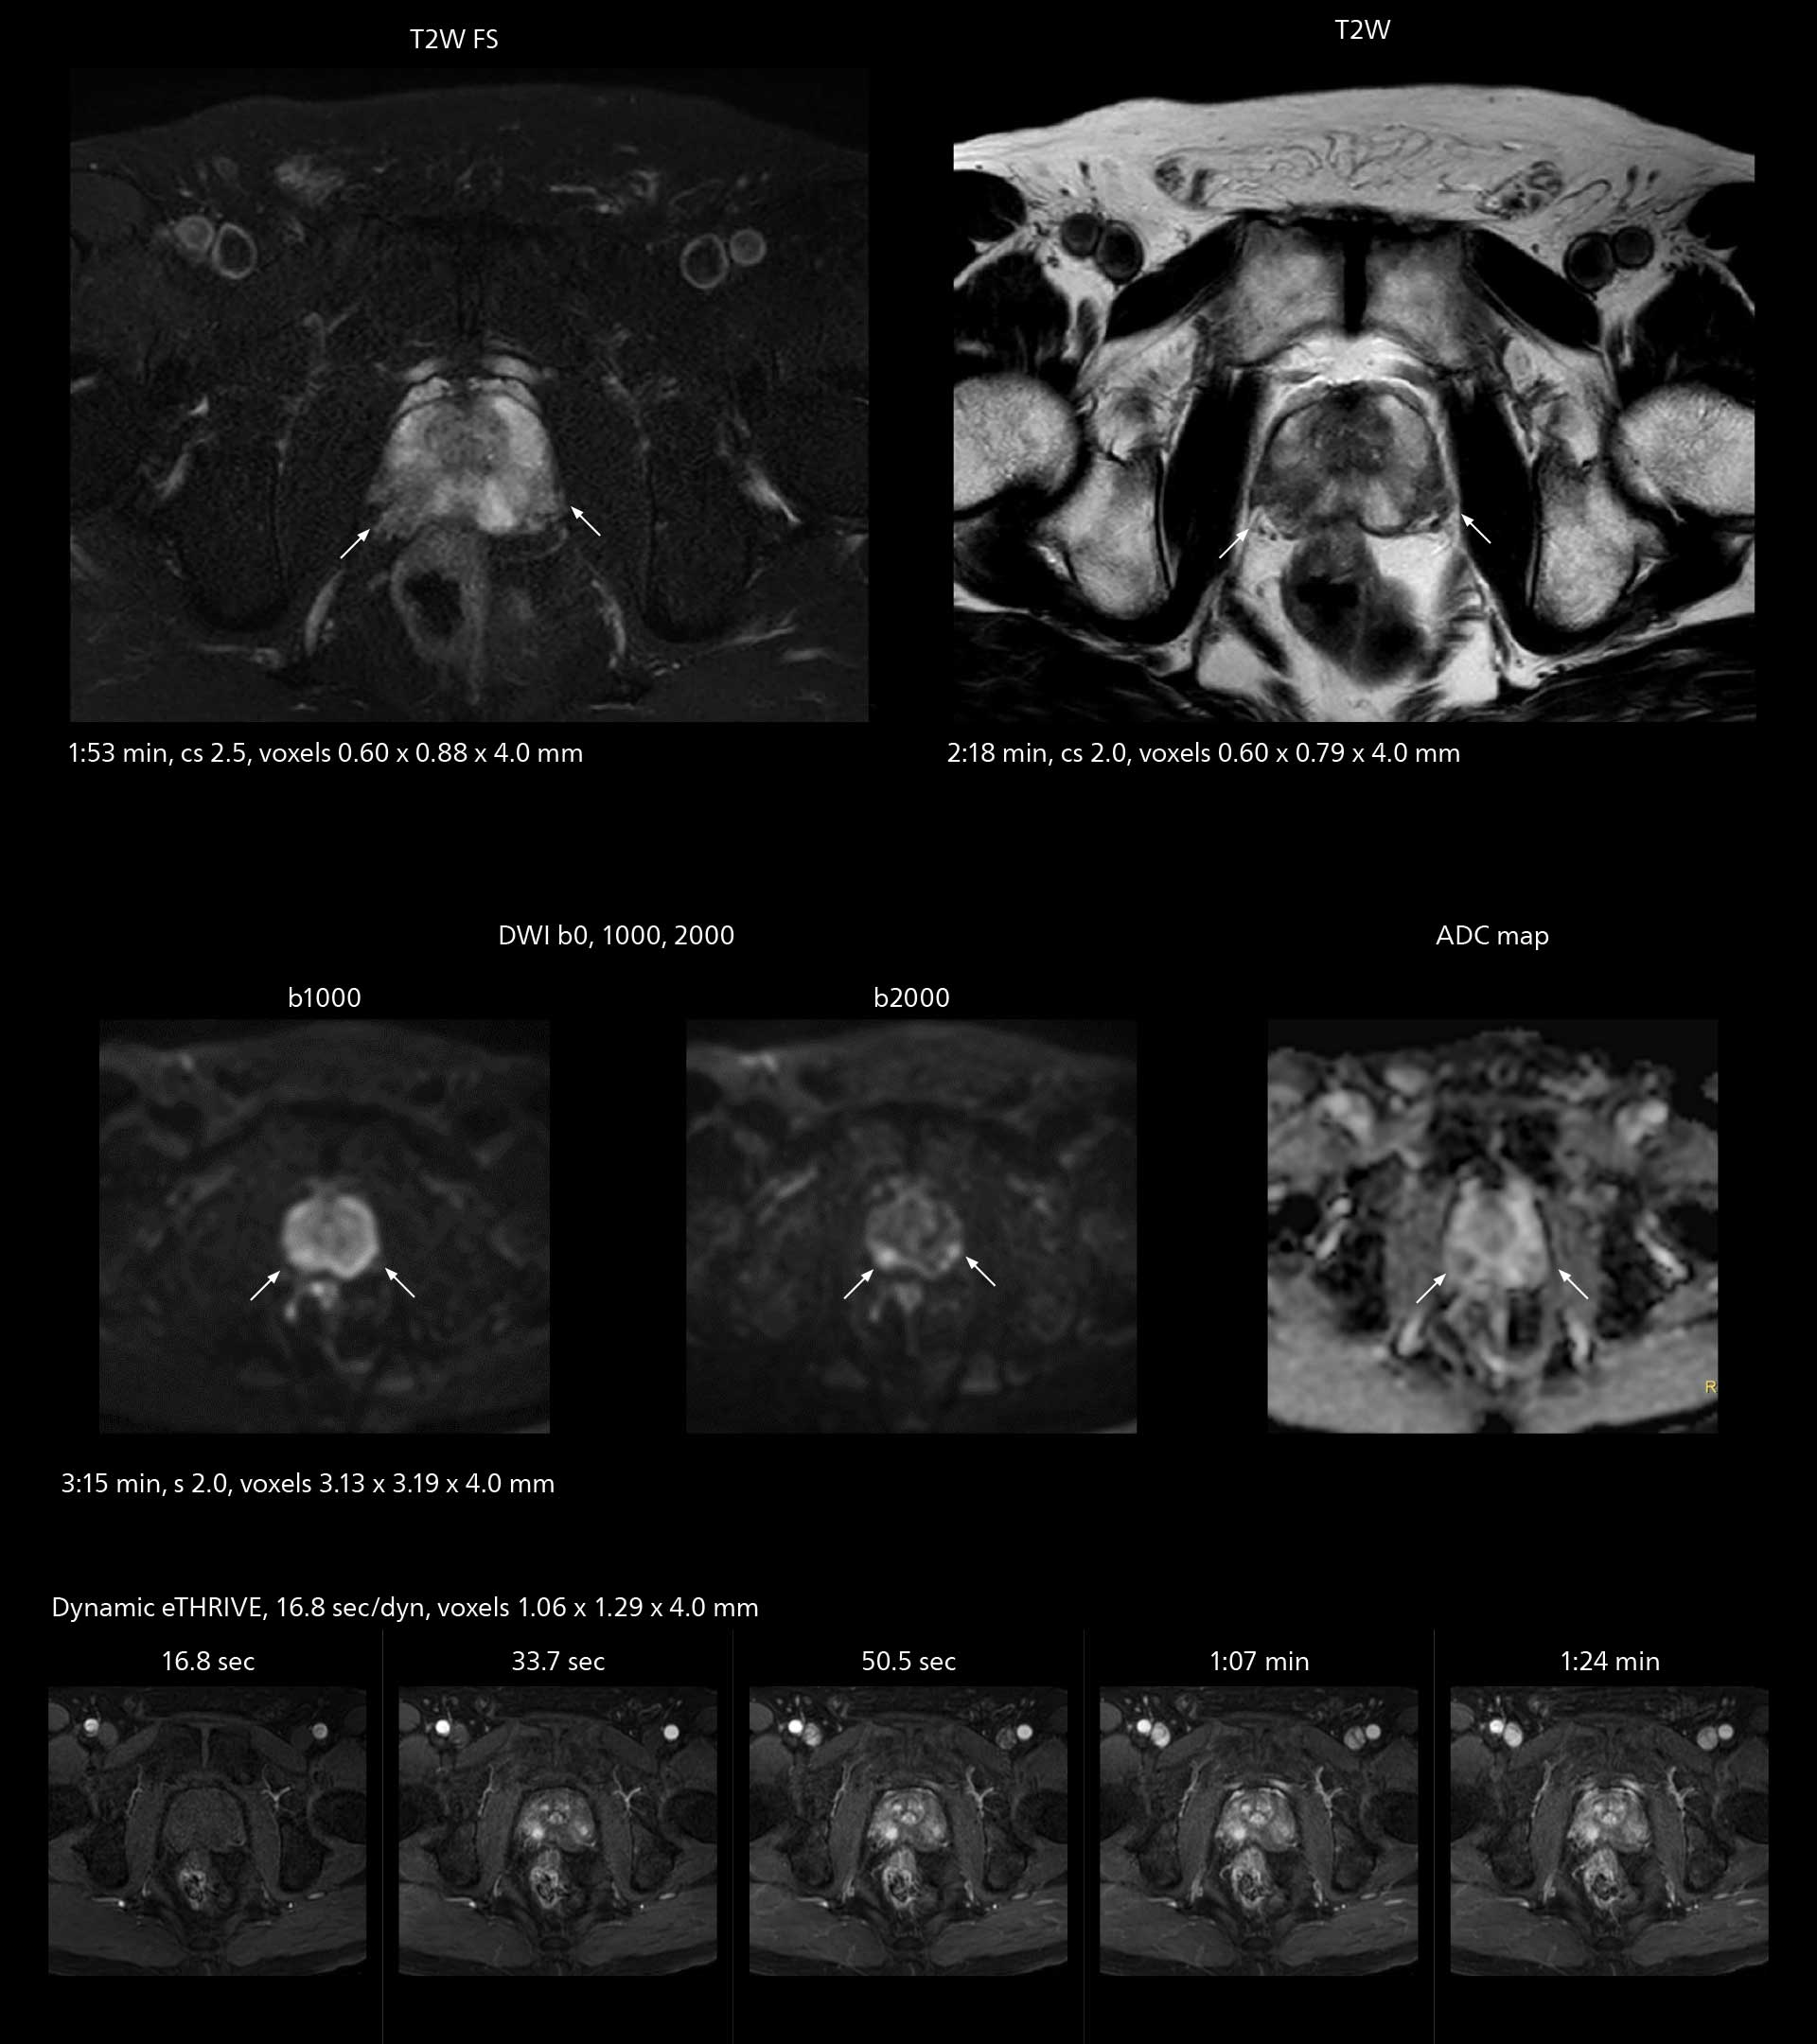

The high performance of the Vega HP gradients is particularly impressive in DWI. “The Vega HP gradients enable us to scan faster and use b-values as high as 2000, for example in prostate DWI and in DWIBS, which provides image quality that is remarkably improved over the previous system and we are able to more easily see lesions.”

MRI of prostate

Examples of prostate imaging showing faster scan times and improved resolution illustrate the power of SmartPath to Elition X in this case of prostate cancer with PI-RADS score 4.